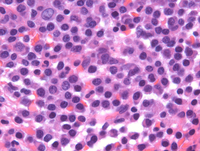

Aspirate smears in myeloma

Aspirate smears are notable for numerous plasma cells occasionally exhibiting anaplastic cytomorphology.